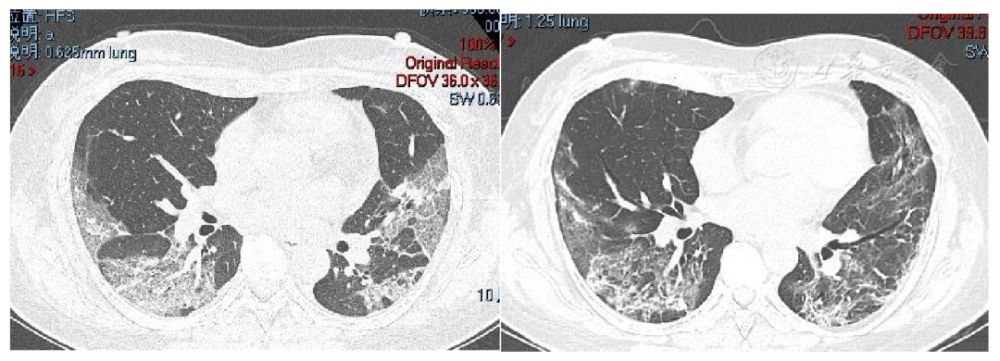

肺纤维化和正常肺图片

肺纤维化和正常肺图片,正常的肺部图片

肺纤维化图片对比

肺纤维化在ct表现图片

肺纤维化的ct图片